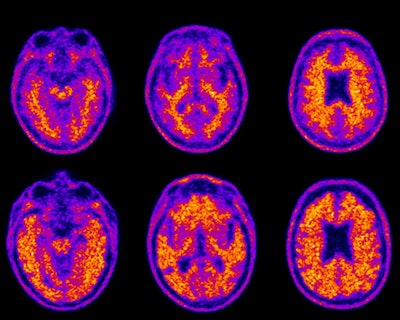

Older adults who have trouble managing their finances also had elevated beta-amyloid levels on florbetapir-PET scans, according to a study from Duke University published online in the Journal of Prevention of Alzheimer's Disease.

FCI-SF total scores were significantly worse in adults with mild cognitive impairment and dementia, compared with normal controls. In addition, more extensive deposition of amyloid-beta plaque on PET scans correlated with a person's inability to comprehend and apply basic financial concepts or to complete tasks such as calculating an account balance.